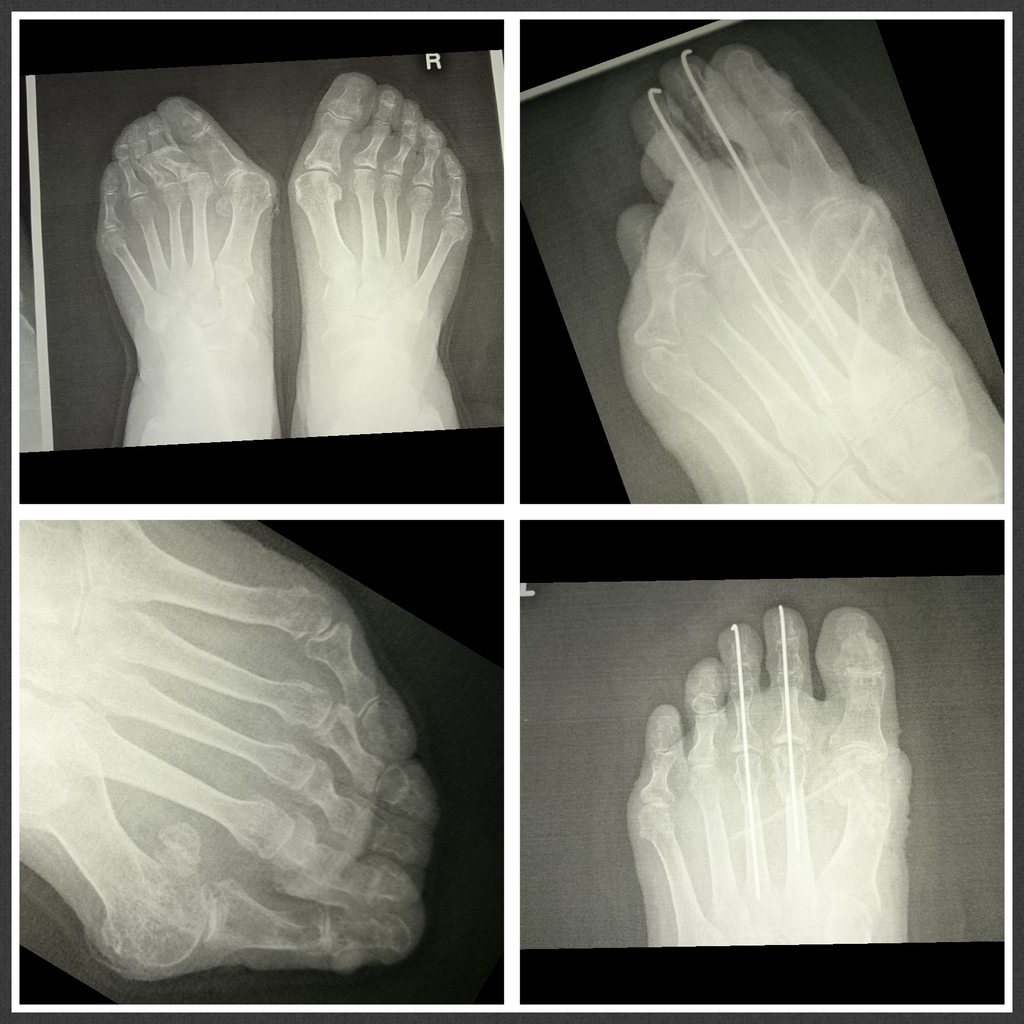

外反母趾

Hallux valgus

外反母趾用の靴として

外反母趾の痛み、変形症状の原因は靴。

原因を作らない靴で快適に痛み悪化を防ぎます。

外反母趾予防、外反母趾対策、

外反母趾対処に。

外反母趾の辛く悪化し続ける痛み、変形症状に対処

痛みを取り、悪化を防ぐ為に足に合わせるオーダーメイド靴

リウマチ・膠原病

Rheumatism

リウマチ、膠原病は不可抗力なご病気。

リウマチの90パーセントは女性が発症

靴が合わない事は勿論、

足が入らない変形と歩行困難などでお困りの方ご相談ください。

リウマチ、膠原病など、靴にお困りの方に足に合う靴、歩行を助けるための靴などご相談に応じます。